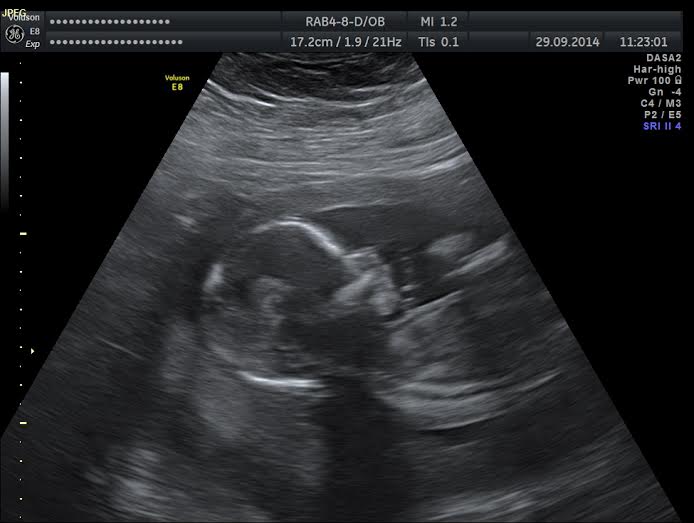

Ahoj holky, dlouho jsm se nehlásila neb jsem se rozhodovala, zda podstoupit amniocentézu či nikoliv. Na dnešek jsem byla objednaná. Ještě cestou do Prahy jsme s přítelem rozmýšleli jestli jo nebo ne. Až tam, jsme se rozhodli, že ano. Po pravdě jsem měla šílený strach. Nakonec to nic nebylo. Teď polehávám tak jak doporučují. Mám 15ti letou dceru a moc jsme si přáli chlapečka po dotazu na paní doktorku co čekáme tak s malou rezervou holčičku takže kluk měl být Ladislav na památku mého tatínka, který nás nedávno opustil bude holčička pravděpodobně Ladislava nebo Lada. Jinak minulý týden jsem prodělala angínu tak snad bude vše ok i výsledky odběru plodovky.

Pokusím se přiložit dněšní foto jsem 16+3